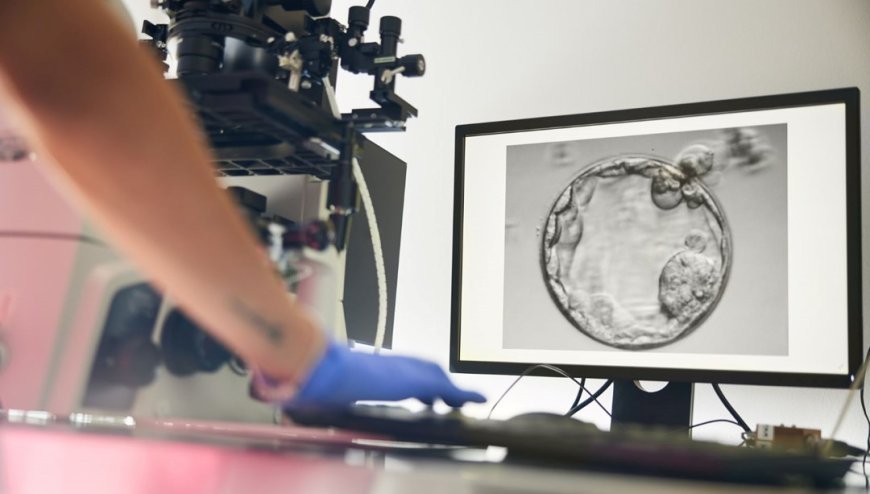

Araştırma ekibi, doğal hücre bölünmesini taklit ederek fazla kromozomları ayıklayan ve geride 23 kromozom bırakan bir yöntem geliştirdi. Bu sürece “mitomeyoz” adı verildi. Ancak üretilen yumurtaların yalnızca yüzde 9’undan daha azı, döllenme sonrası embriyo gelişiminin kritik aşaması olan blastosist evresine (5–6 günlük gelişim) ulaşabildi. Üstelik ortaya çıkan tüm embriyolar kromozom bozuklukları taşıyordu.